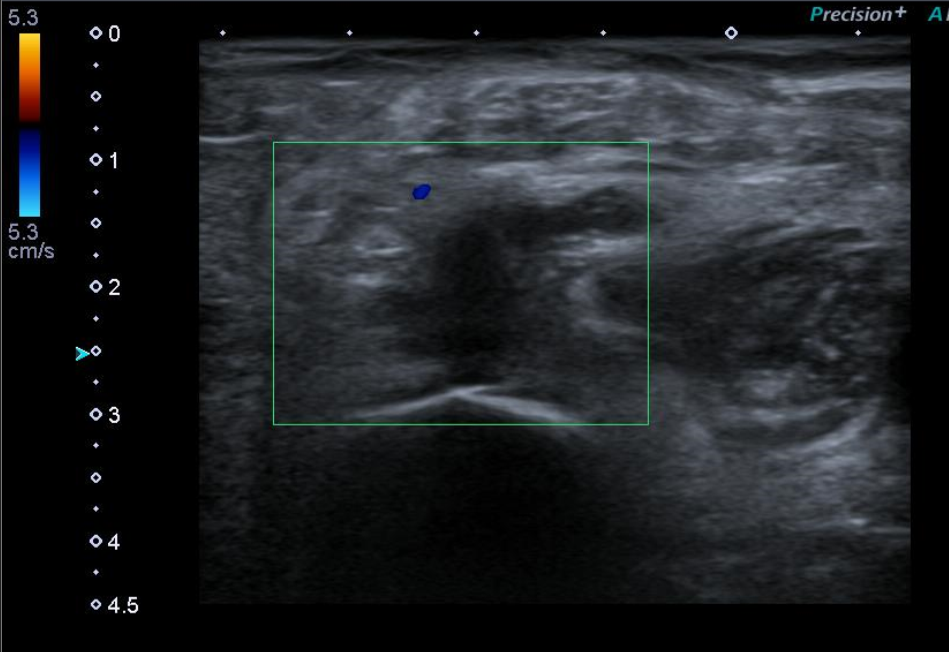

Ecografía Doppler miembros inferiores: venas permeable sin signos de TVP. En el hueco poplíteo de MID se observa una estructura anecoica de aproximadamente 17 x 14 mm (AP x T), con restos hiperecogénicos en su interior y cuyo polo inferior muestra una morfología irregular afilada, observándose láminas de líquido adyacentes. Hallazgos compatibles con rotura de quiste popliteo (de Baker).